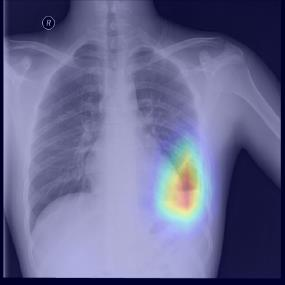

Chest X-ray (CXR) is the most typical diagnostic X-ray examination for screening various thoracic diseases. Automatically localizing lesions from CXR is promising for alleviating radiologists' reading burden. However, CXR datasets are often with massive image-level annotations and scarce lesion-level annotations, and more often, without annotations. Thus far, unifying different supervision granularities to develop thoracic disease detection algorithms has not been comprehensively addressed. In this paper, we present OXnet, the first deep omni-supervised thoracic disease detection network to our best knowledge that uses as much available supervision as possible for CXR diagnosis. We first introduce supervised learning via a one-stage detection model. Then, we inject a global classification head to the detection model and propose dual attention alignment to guide the global gradient to the local detection branch, which enables learning lesion detection from image-level annotations. We also impose intra-class compactness and inter-class separability with global prototype alignment to further enhance the global information learning. Moreover, we leverage a soft focal loss to distill the soft pseudo-labels of unlabeled data generated by a teacher model. Extensive experiments on a large-scale chest X-ray dataset show the proposed OXnet outperforms competitive methods with significant margins. Further, we investigate omni-supervision under various annotation granularities and corroborate OXnet is a promising choice to mitigate the plight of annotation shortage for medical image diagnosis.